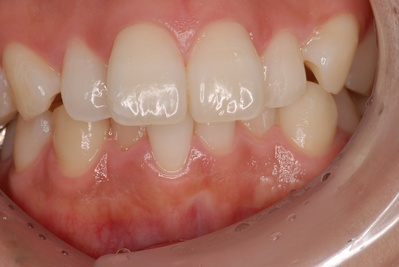

上の左右2番目の歯が内側にたおれているのをきれいにしたいという患者さんでした。

最初の状態

矯正をするか、かぶせで治すか、ということでいろいろ話合い、ラミネートべニアで治療しようということに決まりました。